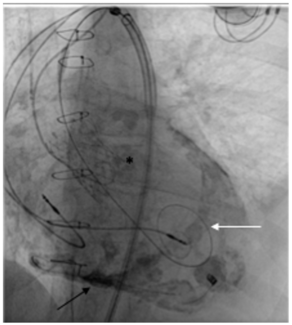

An 80-year-old man was admitted for acute coronary syndrome with ST elevation in the anterior leads. Primary percutaneous coronary intervention (PCI) was performed on the left anterior coronary artery by implanting 3 drug-eluting stents....